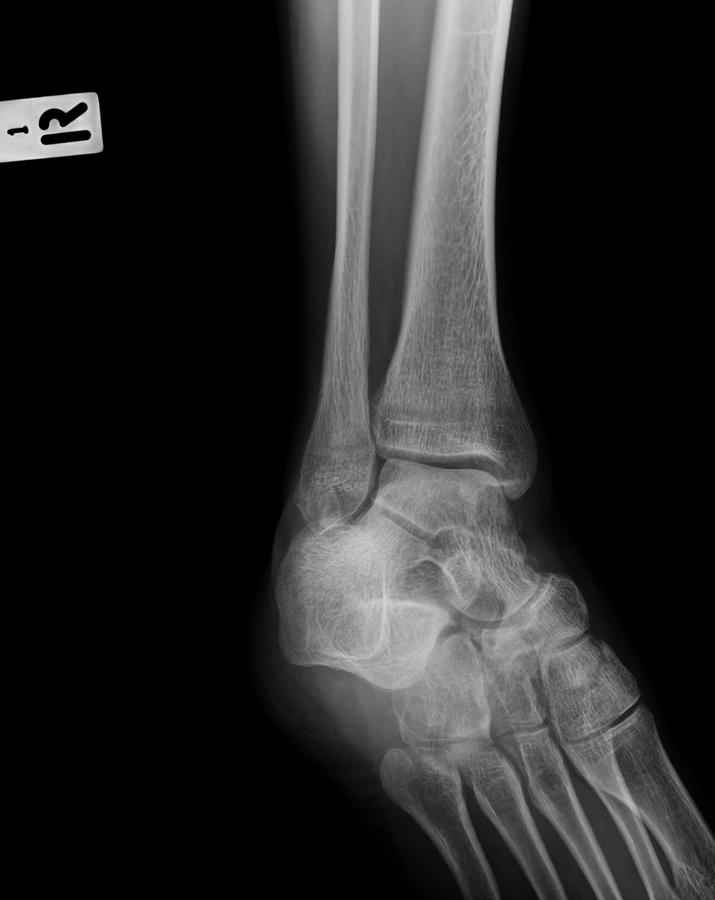

Дорогие коллеги,Мужчина 36 лет, пострадал около 8 месяцев назад в ДТП (водитель мотоцикла).

Подтаранный вывих лечили гипсовой лонгетой. Недиагностированным остался перелом ладьевидной кости, который беспокоит в настоящее время. Аваскулярный некроз кости, похоже. Добавил наиболее значимые снимки, на мой взгляд.

По данным снимкам однозначно сказать о некрозе ладьевидной кости нельзя. Типичные изменения при аваскулярном некрозе ладьевидной кости, как правило, начинаются в центральной её части с дальнейшим развитием коллапса. В данном случае в значительной степени пострадал таранно-ладьевидный сустав, вероятнее всего, именно это является причиной болевого синдрома. При отсутствии эффекта от физиотерапии и ношения ортопедической обуви в течение ближайших 6 месяцев придётся ставить вопрос о таранно-ладьевидном артродезе.